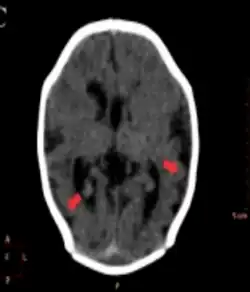

Pachygyria arrow

Different imaging modalities are commonly used for diagnosis. While computed tomography (CT) provides higher spatial resolution imaging of the brain, cerebral cortex malformations are more easily visualized in vivo and classified using magnetic resonance imaging (MRI) which provides higher contrast imaging and better delineation of white and gray matter.[7]

Diffuse pachygyria (a mild form of lissencephaly) can be seen on an MRI as thickened cerebral cortices with few and large gyri and incomplete development of the Sylvian fissures.[3]